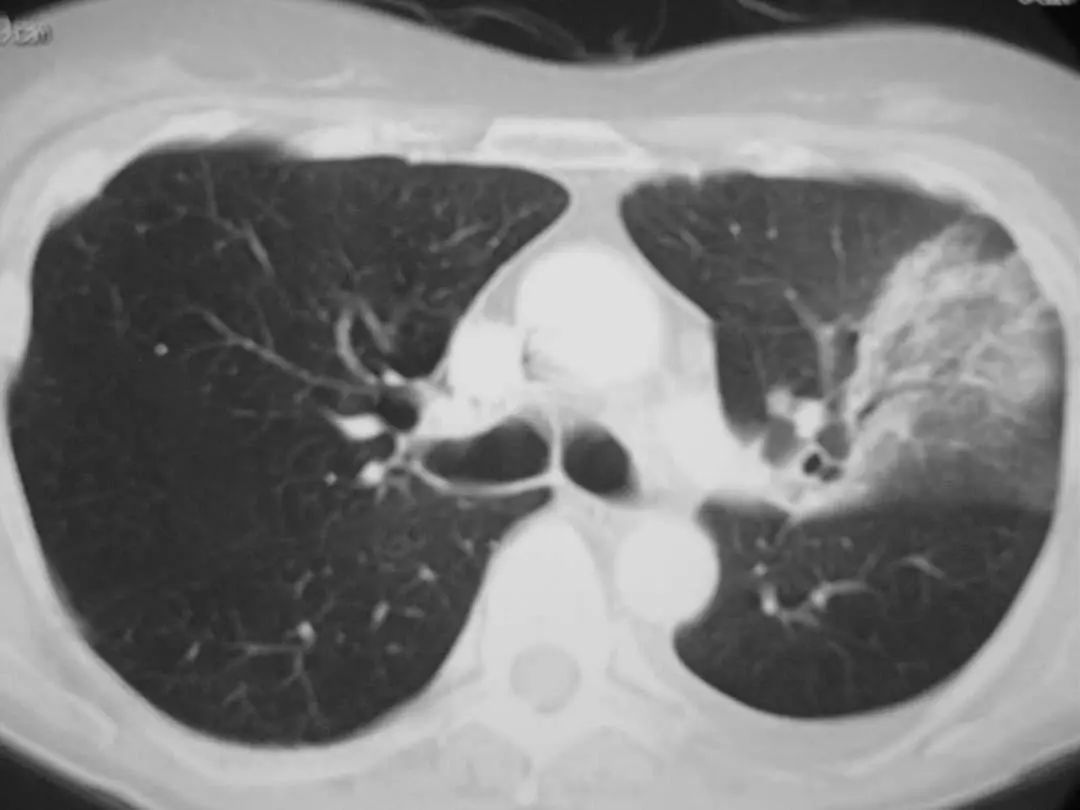

图1.7 CT扫描显示左下叶模糊的气腔浸润。

图1.8 45岁的衣原体肺炎患者的胸部CT扫描显示右上叶浸润。

图1.9 49岁肺炎球菌性肺炎患者, 胸部X线片显示左下叶不透明伴胸腔积液。

图1.10 48岁的流感嗜血杆菌性肺炎患者, 胸部X线片显示双侧不透明,主要分布在外周。

图1.11 49岁的肺炎球菌性肺炎患者, 胸部CT显示左上叶不透明延伸至外周。

图1.12 50岁流感嗜血杆菌肺炎患者胸部CT。显示左下叶胸膜附近有致密圆形实变。